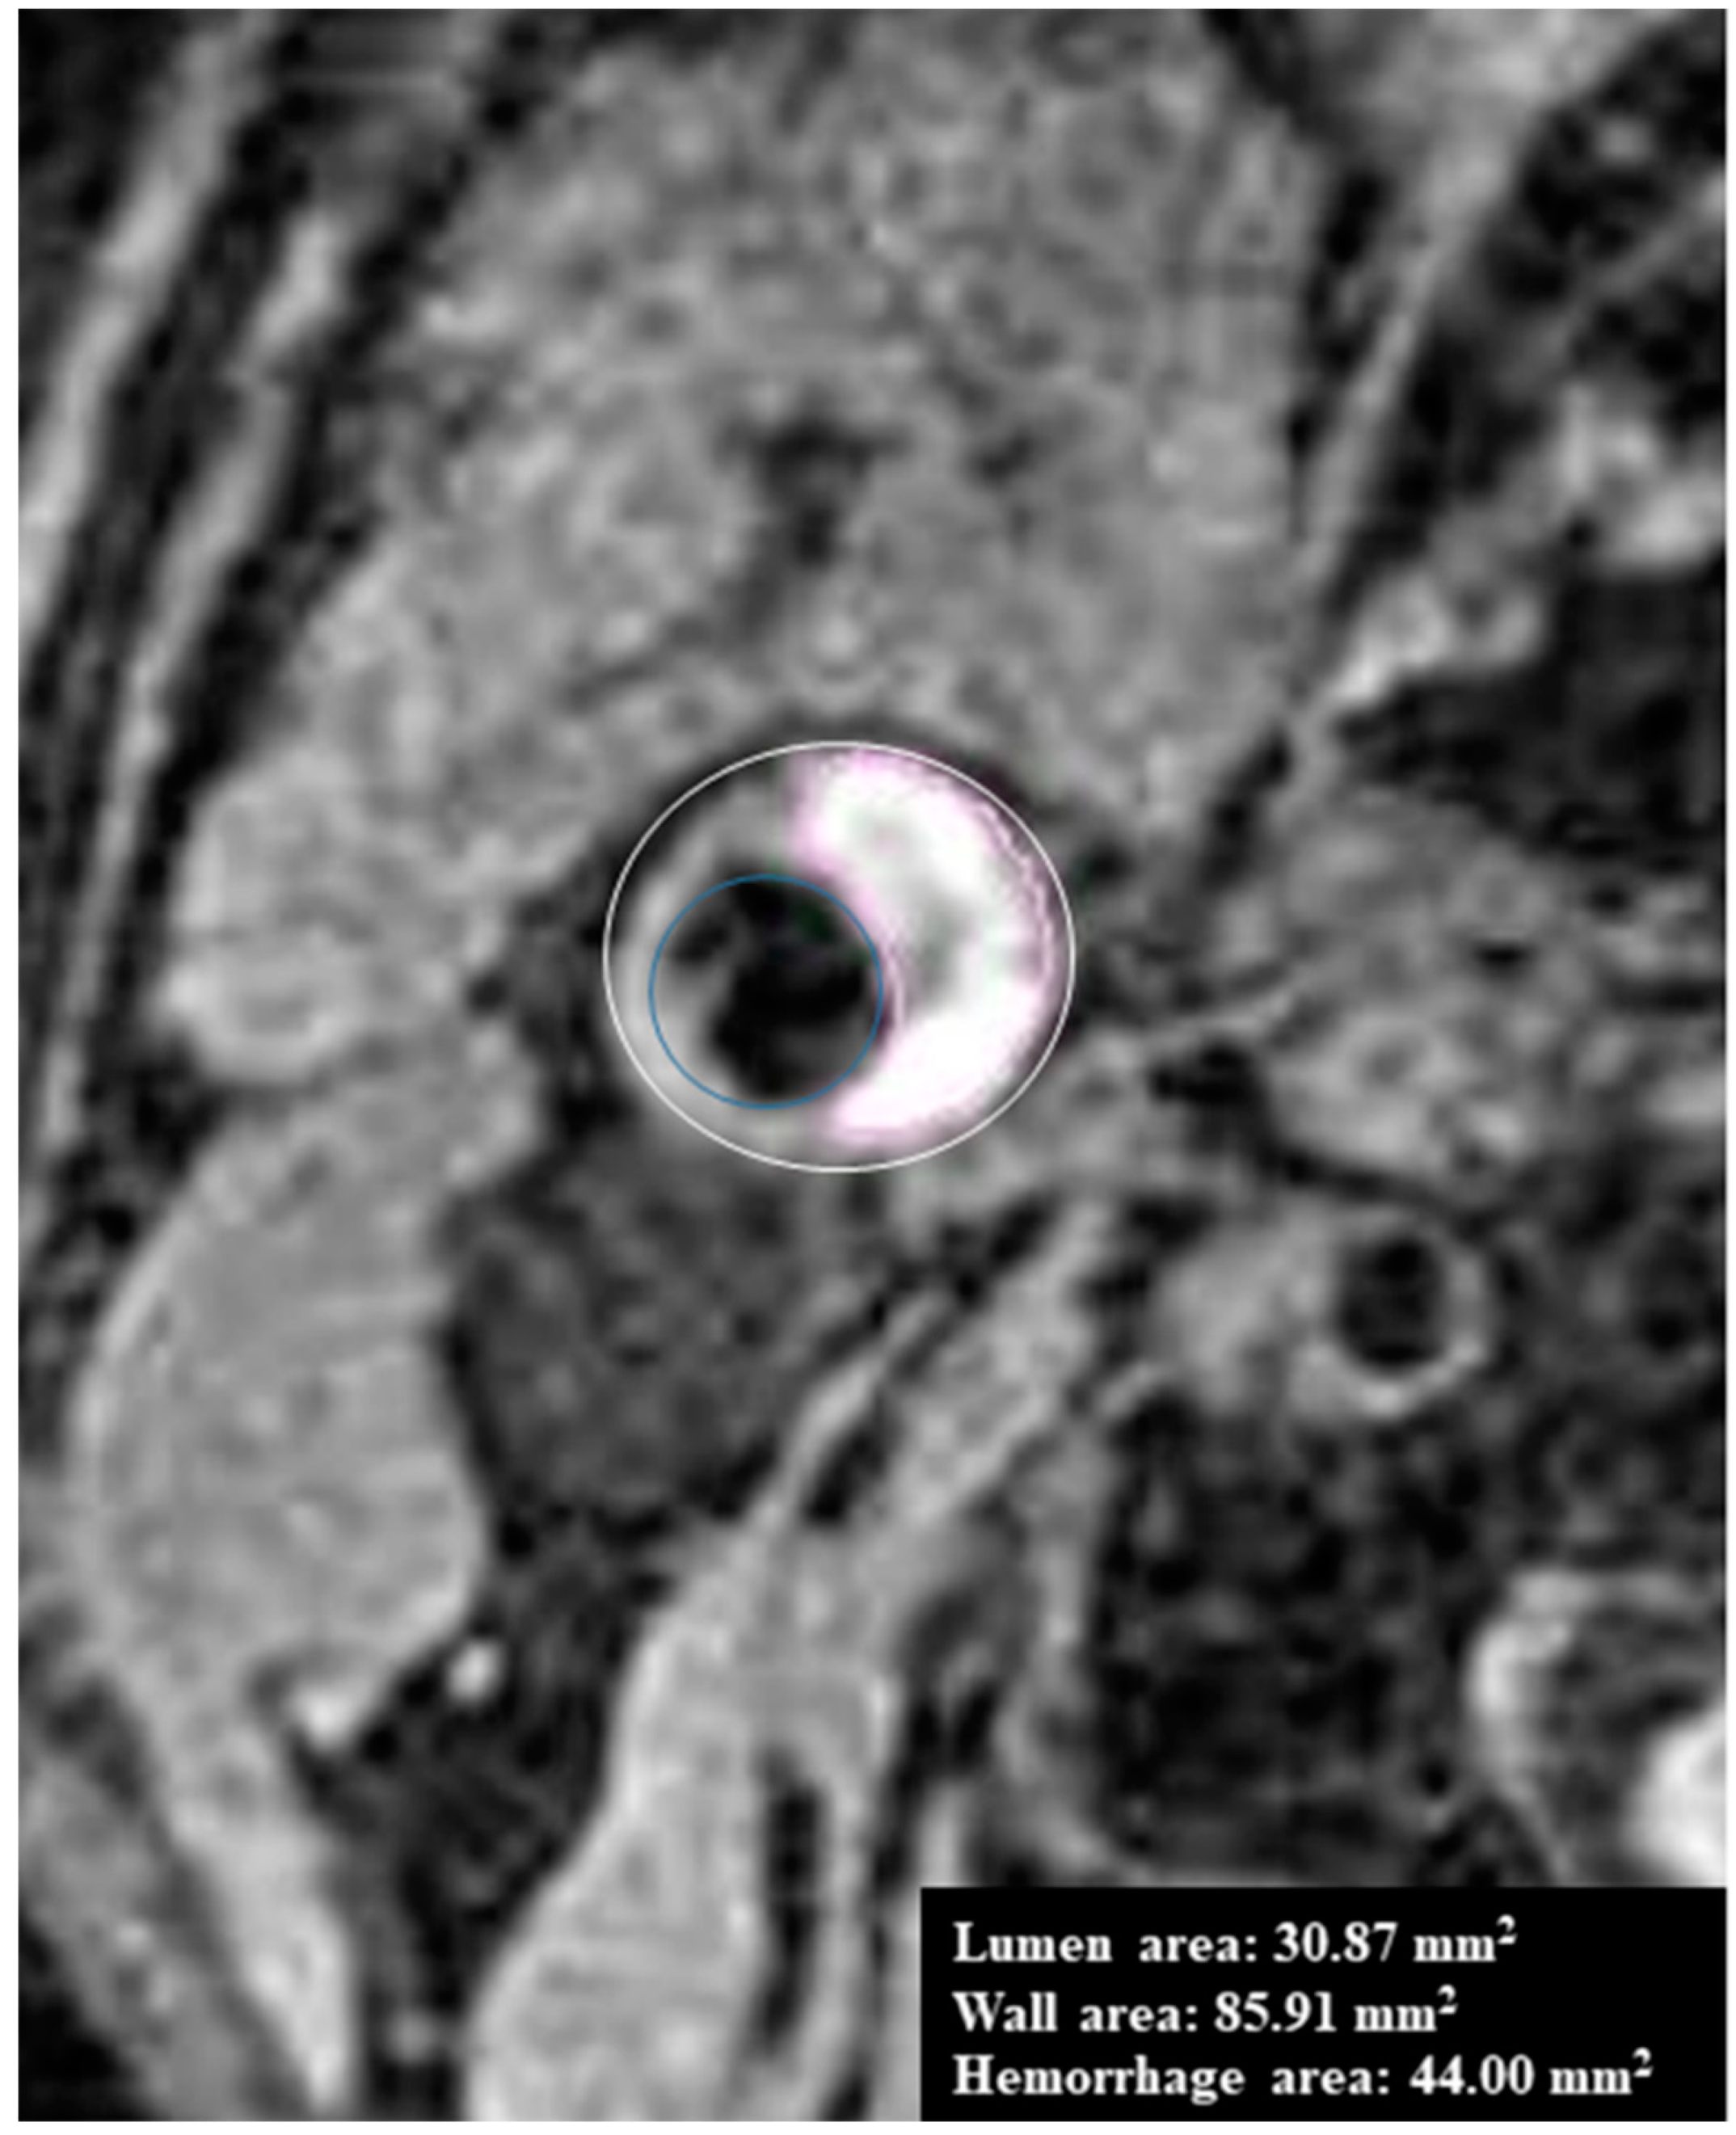

- Liu, J.; Balu, N.; Hippe, D.S.; Ferguson, M.S.; Martinez-Malo, V.; DeMarco, J.K.; Zhu, D.C.; Ota, H.; Sun, J.; Xu, D.; et al. Semi-automatic carotid intraplaque hemorrhage detection and quantification on Magnetization-Prepared Rapid Acquisition Gradient-Echo (MP-RAGE) with optimized threshold selection. J. Cardiovasc. Magn. Reson. 2016, 18, 41. [Google Scholar] [CrossRef] [PubMed]